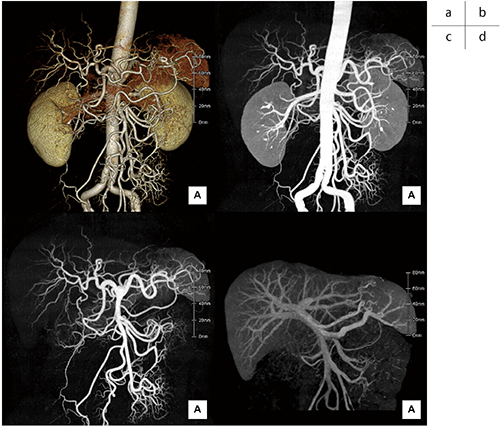

図5 術前3D画像の例

a:動脈VR画像

b:動脈MIP画像(大動脈あり)

c:動脈MIP画像(大動脈なし)

d:門脈MIP画像